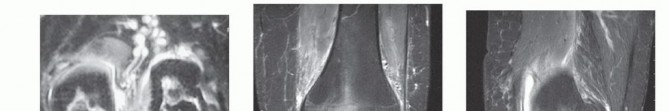

Magnetic resonance imaging (MRI) is an essential part of the diagnostic evaluation of OCD.

It provides critical information regarding the status of cartilage and subchondral bone, size of the lesion, presence of fluid beneath the lesion, extent of bony edema as well as loose bodies or other knee injuries (

FIG 6E,F

).

FIG 6 • A,B. AP and lateral views demonstrating a lesion in the medial femoral condyle. C,D. AP and tunnel views demonstrating an OCD lesion of the lateral femoral condyle. The femoral condyles are in greater profile in the tunnel view, making the lesion easier to appreciate. E,F. Coronal and sagittal MRI images of an OCD lesion. Note the joint fluid present beneath the lesion.